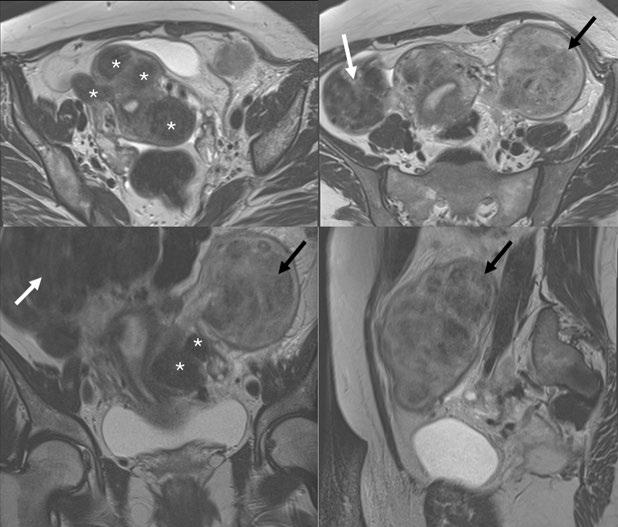

If you like it,why not share it...

Share with a colleague today

Turn static files into dynamic content formats.

Create a flipbook

EMJ 9.4 2024 by European Medical Journal - Issuu